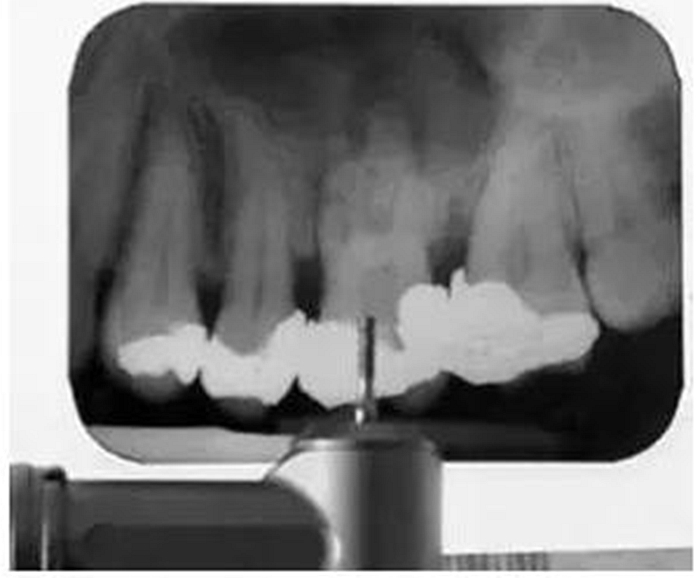

根尖周X線片必須要有最小的失真率和放大倍率,因為任何伸長和透視縮短都會導(dǎo)致根管長度測量的錯誤。對牙根進行仔細的評估是必不可少的,因為可能有畸形牙根(圖1)。在中國患者中發(fā)現(xiàn)C形根管或其他蒙古人種特征的畸形牙根和根管是很常見的。因此,對X線片進行全面評估以確定是否存在額外的牙根或根管是必要的,由此我們可以判斷治療的難度系數(shù)。

它還有助于臨床醫(yī)生決定他是否有能力進行該病例的治療還是應(yīng)該將患者轉(zhuǎn)診到??漆t(yī)生處進行治療。還可以在治療前明確髓腔內(nèi)是否有髓石以及牙齒或根管內(nèi)是否有其他阻塞物(如樁、釘、分離的儀器或根填充材料)(圖2)。這是很重要的,因為它會給臨床醫(yī)生一些預(yù)后和治療中可能出現(xiàn)的一些問題的提示。所有這些因素必須在治療前與患者進行溝通,以便其決定是否要繼續(xù)進行根管治療。

如果根管內(nèi)有樁、折斷的器械或根充物,那么該患牙的治療難度就會增加(圖3)。樁能否從根管內(nèi)取出取決于樁的大小和形態(tài)。如果根管內(nèi)的折斷的器械位于根尖三分之一和彎曲根的根方,將折斷器械取出來的難度要比在冠方的更困難。